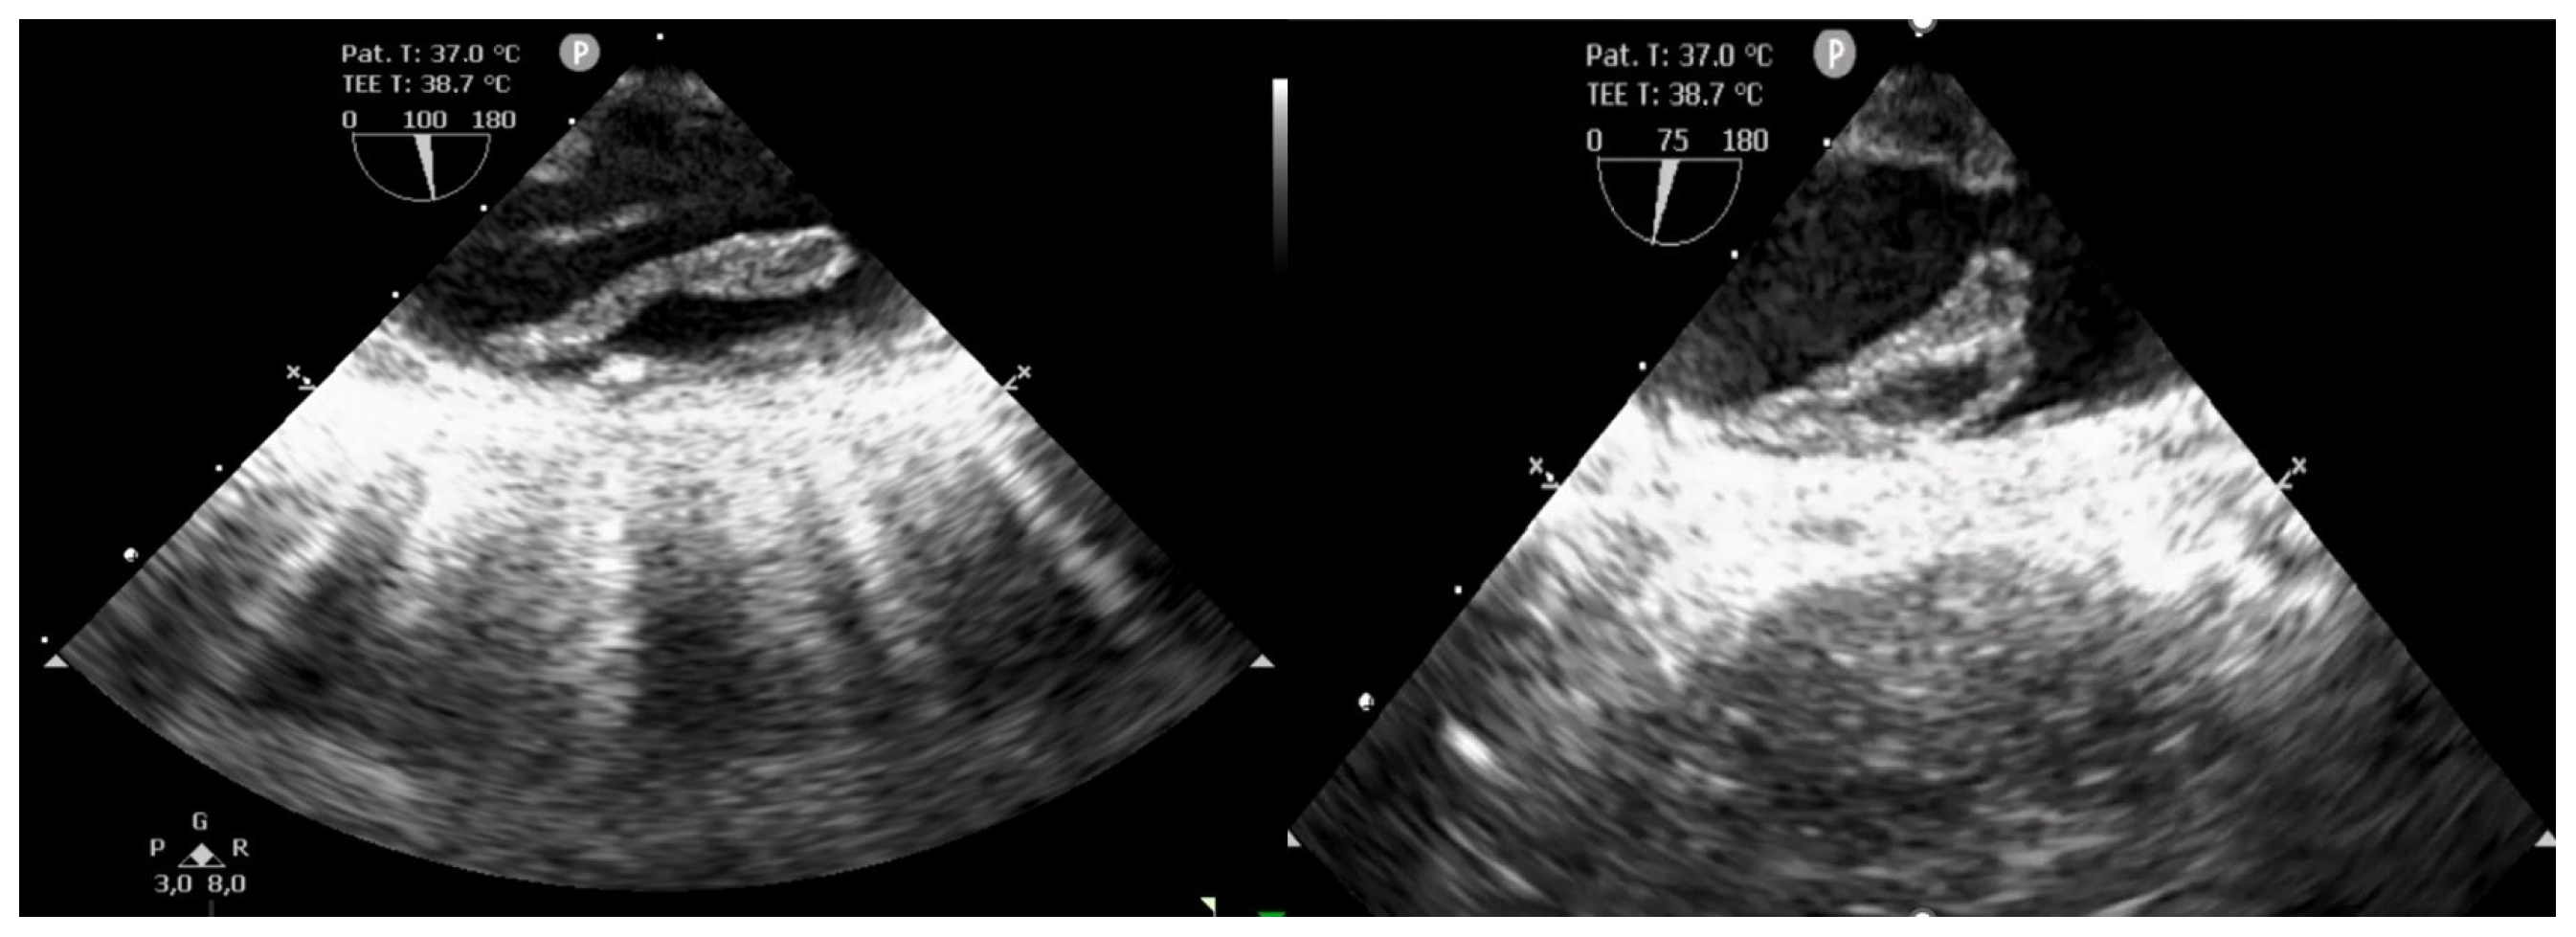

2. Case Presentation